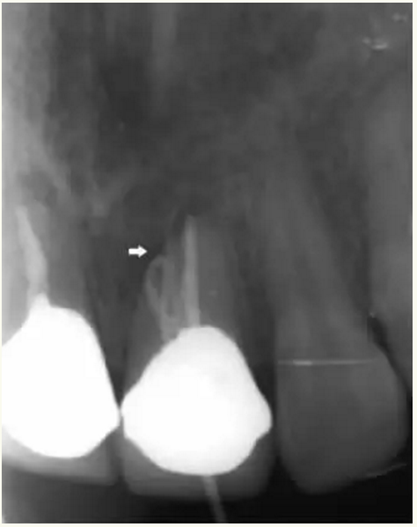

▲術(shù)后,X線顯示:21根尖切除區(qū)域骨質(zhì)修復(fù),根管倒充填物完好,原牙周膜間隙增寬影消失